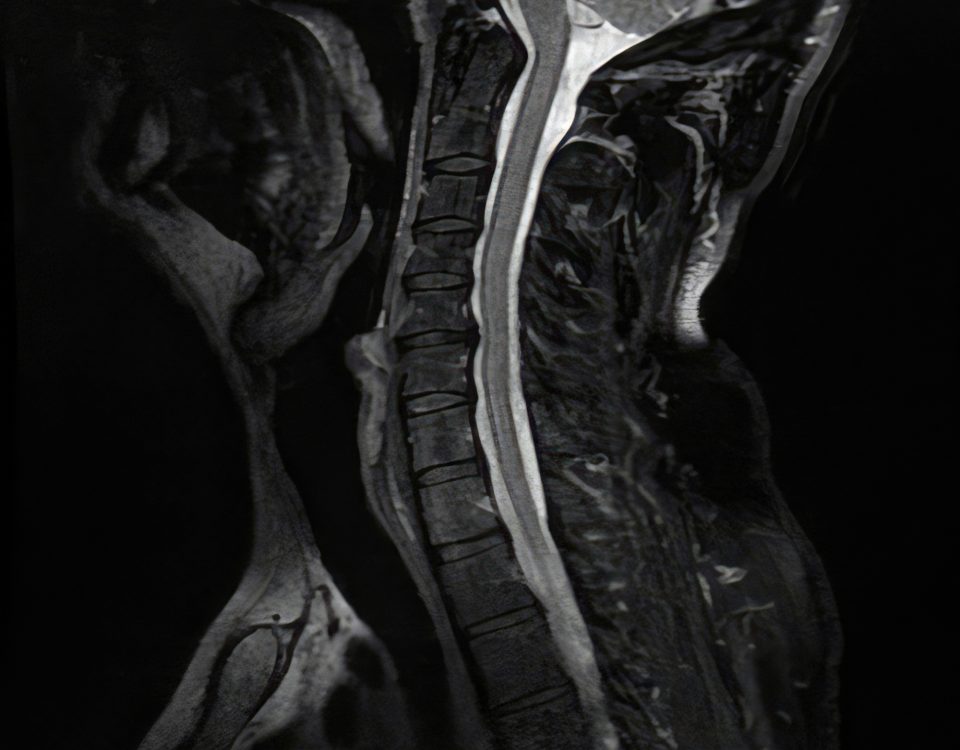

La catégorie « Chirurgie cervicale » regroupe l’ensemble de nos articles et pages consacrés aux pathologies et traitements chirurgicaux du rachis cervical. Vous y trouverez des informations détaillées sur les différentes affections touchant la région du cou, telles que l’hernie discale cervicale, la myélopathie, la cervicarthrose ou les traumatismes, ainsi que sur les innovations en matière de prise en charge : prothèse discale cervicale (arthroplastie), arthrodèse, microchirurgie, techniques mini-invasives, indications, déroulement des interventions et suites opératoires. Cette section vise à informer et accompagner les patients et leurs proches dans leur parcours de soins, en présentant de façon claire et actualisée les options de chirurgie cervicale les plus modernes, permettant de soulager la douleur, préserver la mobilité et optimiser la récupération fonctionnelle.